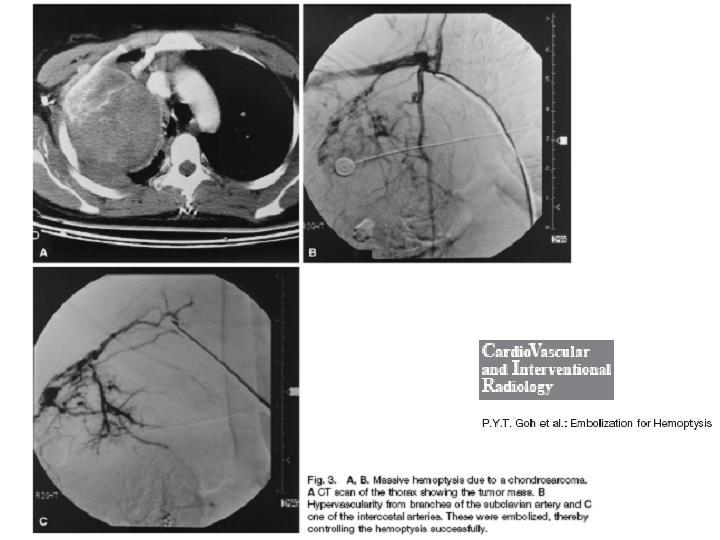

Hemoptisis Masiva

Cirugía Cardíaca